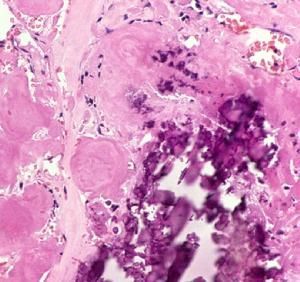

1、澱粉樣纖維蛋白:澱粉樣蛋白是一種無定形的玻璃樣透明物質,蘇木精染色呈淺粉紅色,剛果紅染色呈磚紅色,在偏光顯微鏡下為蘋果綠色雙摺光現象,電鏡下可見由非分支的小纖維排列而成,澱粉樣纖維蛋白包括以下8種成分,其中以AL蛋白及AA蛋白為主要成分。

2、腎活檢:根據腎活檢做病理檢查,標本以剛果紅染色,一般光學顯微鏡足以明確診斷。

5、病理學檢查:病理學檢查是確診的最可靠方法。內臟穿刺活檢使生前診斷率大為提高。蛋白尿明顯者,腎臟活檢陽性率接近為100%。腎活檢後易出血,但不如肝活檢出血嚴重,故目前認為腎活檢較肝活檢更為可取,已成為診斷腎澱粉樣變性病的主要手段。活檢標本經5%高錳酸鉀處理後再進行剛果紅染色,AA蛋白對高錳酸鉀敏感,與剛果紅之親和力小,著色試驗為陰性,而AL蛋白與剛果紅之親和力大,著色試驗為陽性,故可用此法鑑別病變系由AA蛋白或AL蛋白所致,故有助於區分原發性與繼發性澱粉樣變性。